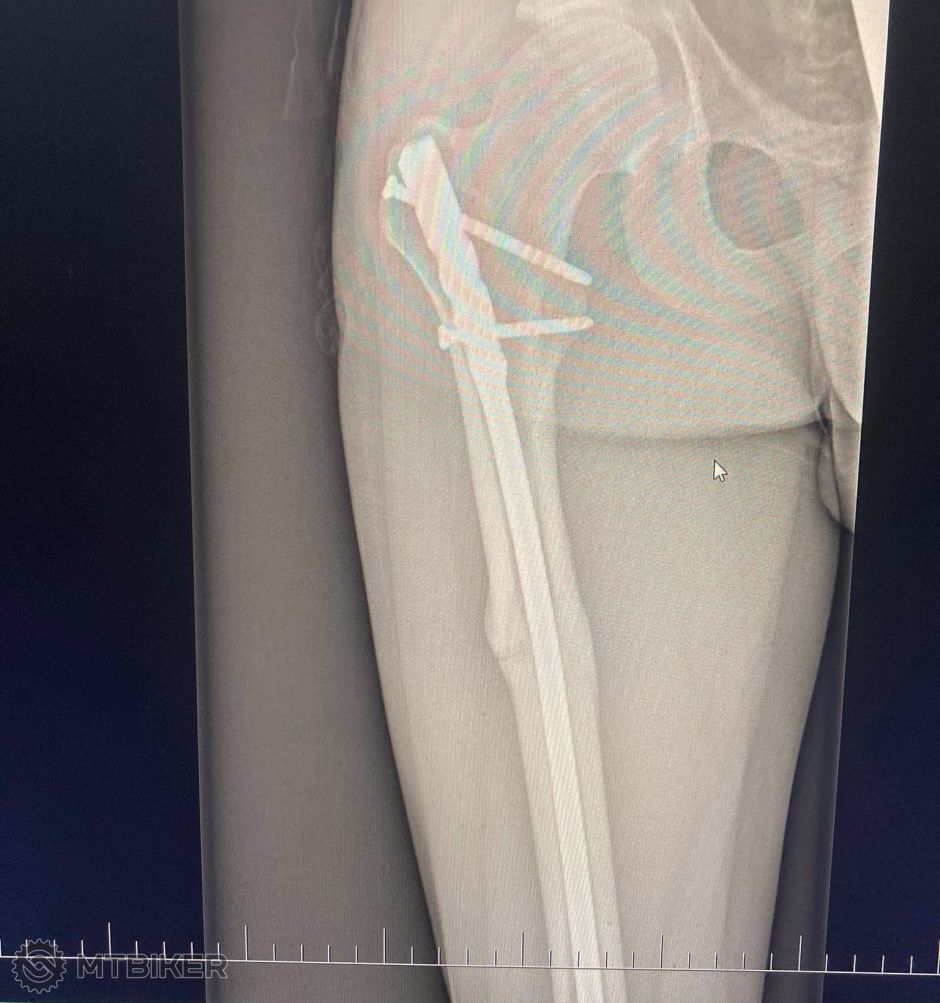

Kaper ta snimka rtg napravo na monitore to mas zlomeny krcok stehennej kosti ? Ako sa ti dari, ako sa to hoji?

Snimka potvrdila zlomeny krcok stehennej kosti... V ten isty den operacia - mali mi tam dat 2 sroby, snimok som este nevidel - bude pri dalsej kontole.